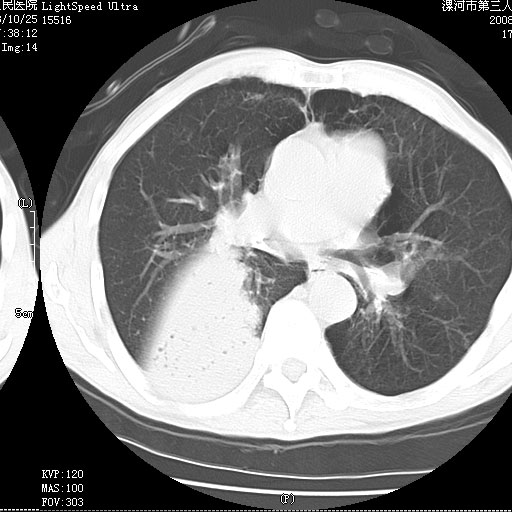

m 老年 发烧、呼吸困难,慢支、肺气肿多年;记的那次是下午大概17:38做的,晚上窒息死亡。

上面的层面就慢性支气管炎肺气肿、肺大泡,别的没有什么、也就不传了。

当时我怀疑:1、阻塞性肺不张早期 2、肺脓肿早期,望老师们发表意见

应该是脓胸的表现,右下肺气管阻塞考虑为痰栓.

你怀疑的有道理,慢支、肺气肿、肺打泡是有了,右下肺的病变有待商议;

首先考虑右下肺炎症并不张,不除外早期肺泡癌改变

病灶边缘清---多个含气小腔---近端未见通畅气管影-----支持-----慢性肺脓肿继发阻塞性肺不张

阻塞性肺不张原因-----脓液未排出

1、右侧脓胸;2、copd;

3、细支气管肺泡癌可以排除,病变以斜裂为界,呈大片状高密度影,内可见多发小气泡,表明有产气杆菌感染所致,内无明显的支气管“枯树枝征”表现,再结合其临床改变(细支气管肺泡癌临表表现重、影像表现轻)所以不符合细支气管肺泡癌(炎症型)的改变。